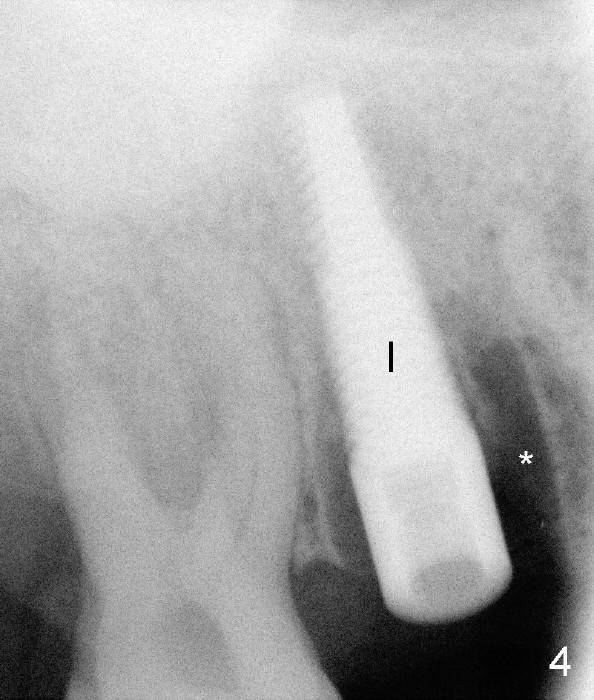

A 51-year-old man requests taking care of hemorrhage and odor associated with the tooth #3 (Fig.1). Due to religious and financial issues, the neighboring teeth will be treated later (supraeruption of #2 (arrow) and periapical radiolucency of #4 (*)). CBCT reveals that the septum of #3 is large enough to hold 4.5 mm implant (Fig.2). In fact osteotomy is created as planned in the septum using drills and taps (Fig.3 after removing 4.5x20 mm tap). Primary stability is obtained with a 4.5x20 mm implant (> 60 Ncm, Fig.4). The gap (*) is bone grafted; an abutment is placed (Fig.5 A); an immediate provisional is fabricated and cemented to cover the socket (Fig.6 P). When the socket heals in 3 weeks postop, the provisional and the abutment are removed for easy oral hygiene. Bone regenerates around the implant 3.5 months postop (Fig.7 *), but the 2nd molar has shifted mesially (arrow), presenting a restoration challenge.

It appears that the upper molar shifting is quite common (6 7), probably due to less dense bone in the maxilla. It is the best to fabricate and keep an immediate provisional to hold the mesiodistal dimension and ask the patient to improve local oral hygiene during osteointegration. The implant crown is functioning 4 years 2 months post cementation while there is severe bone loss at #2 (Fig.8). An immediate implant could be placed at #2 (Fig.9), while a wide delayed implant will be placed at #31 (Fig.10).